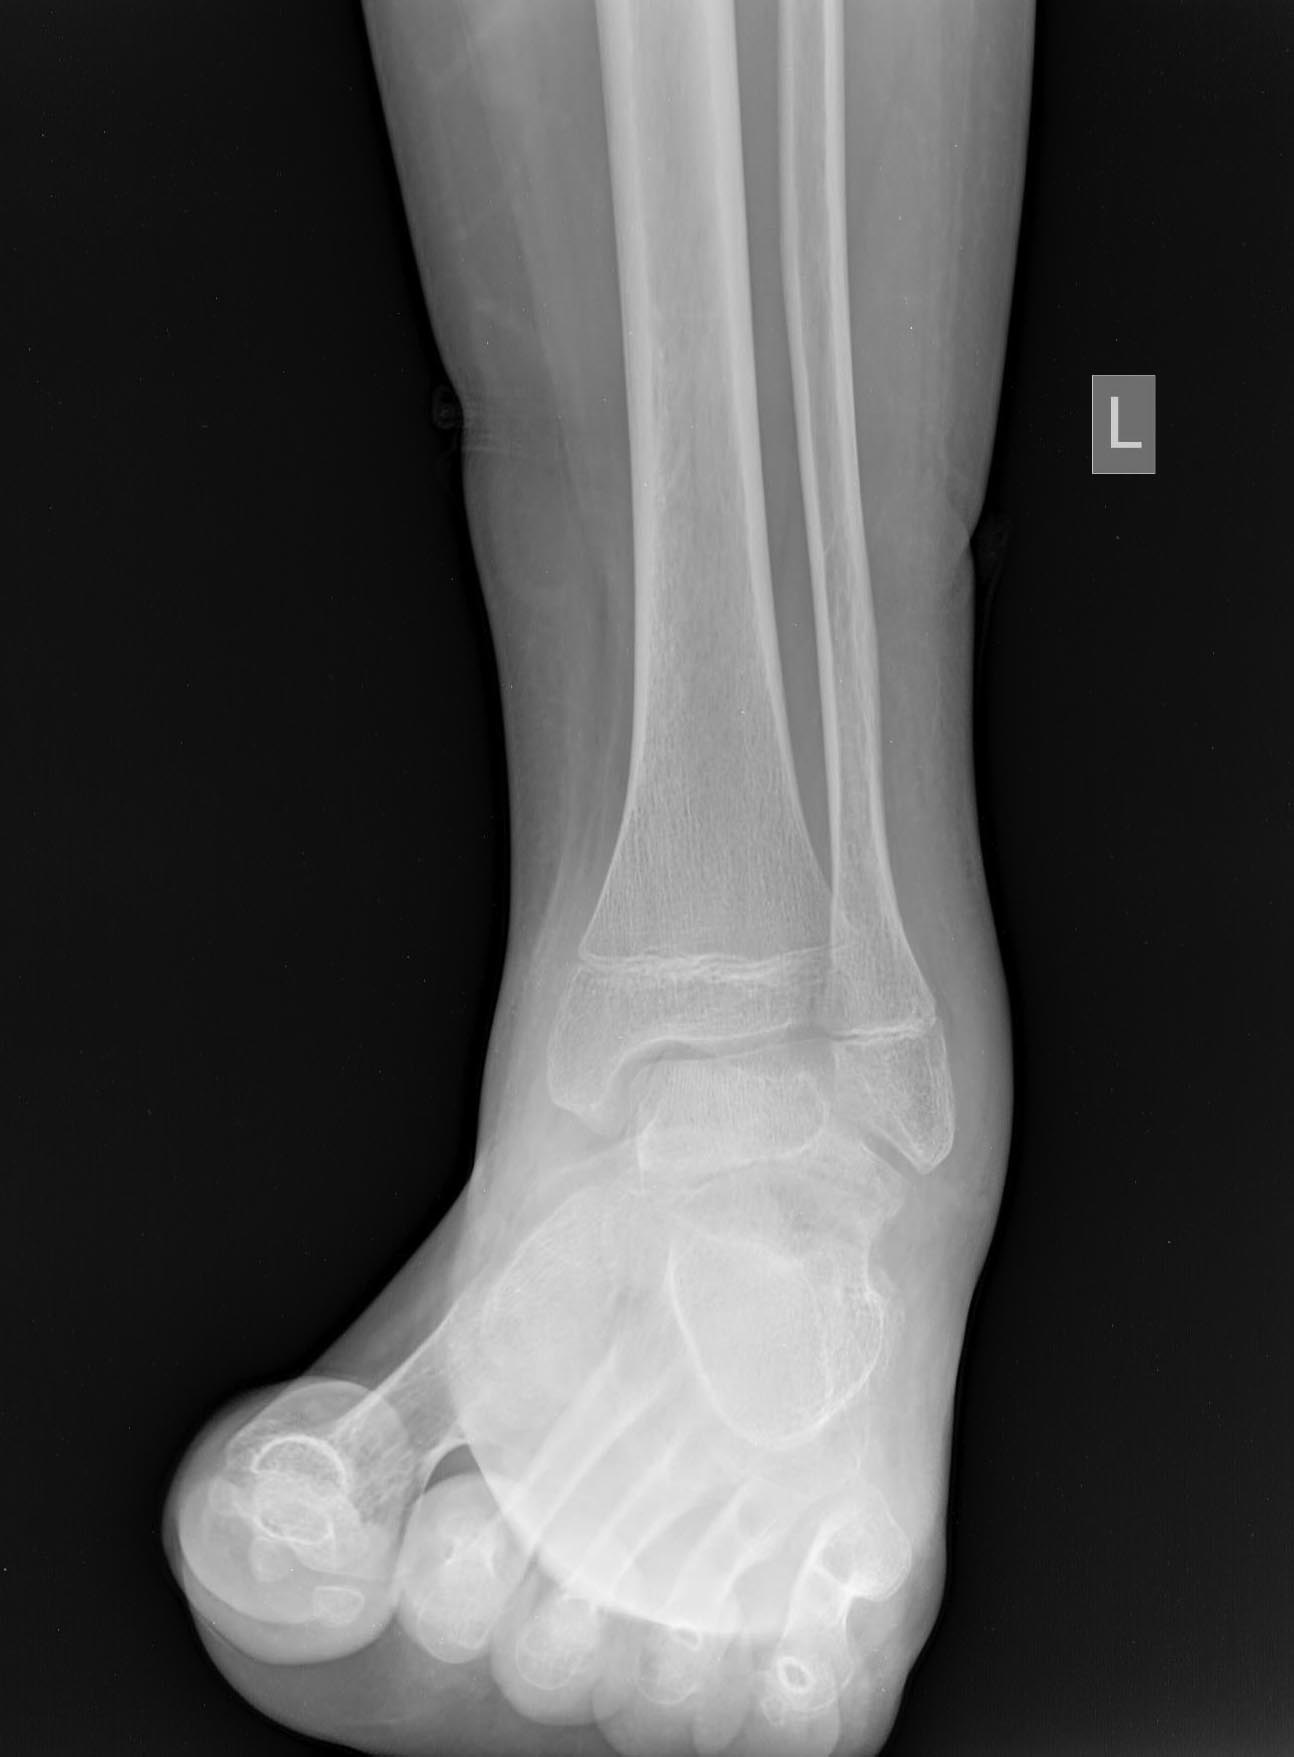

Нелеченный перелом шейки таранной кости у 14-летнего подростка

Травма 2 мес. назад. На снимках перелом шейки таранной кости в детской больнице не увидели.

Сказали, мол, растяжение - наступай. Ну вот он и наступает. Сейчас ходит с тростью.

Что делать? Подтаранный артродез с gjgsnrjq сохранить голеностопный сустав, или большеберцово-пяточный блок с использованием остатка таранной кости в качестве трансплантата?

A boy 14 was referred yesterday.

Injured 2 mnth ago, the fracture was missed somewhere, and he was recommended to walk. And he was trying to do this all that time. Now he is able to walk with cane.

Either subtalar fusion with attempt of ankle preservation, or tibio-calcaneal fusion with the use of remnant of the talar dome as a graft?

How would you manage this case?